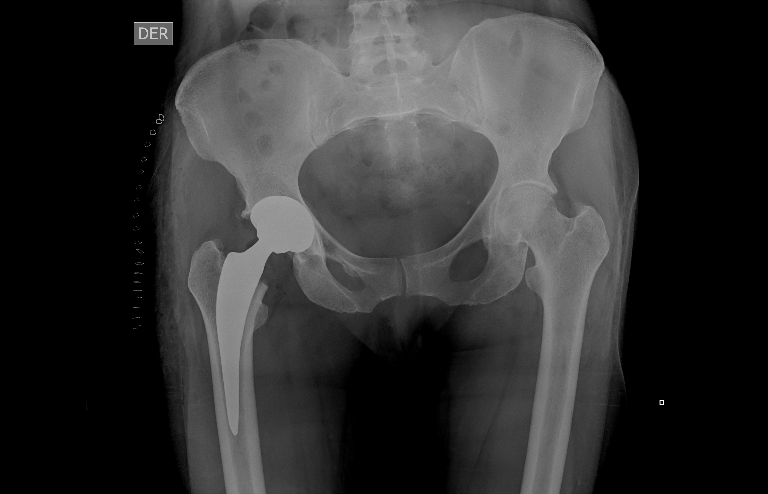

Soy médico cirujano especializado en ortopedia; con una segunda especialidad en cirugía de cadera y preservación articular; enfocado en técnicas mínimamente invasivas, reconstrucción y preservación articular atención personalizada para la preservación articular en pacientes jóvenes y adultos.